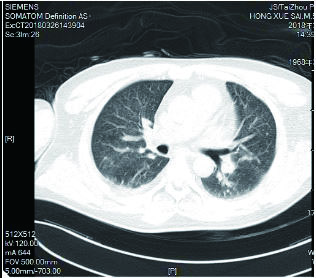

该患者入院后因氧合不能维持、呼吸窘迫直接从急诊收治ICU,大剂量激素冲击及气管插管,呼吸机SIMV+PS模式支持治疗,氧合指数改善不明显,及时行俯卧位通气,但氧合指数仍然小于100,PAO2 38 mmHg, SpO2 78%左右,考虑患者病情危重,且血流动力学不稳,血管活性药剂量大,当天下午行V-V模式ECMO治疗(右侧颈静脉-右侧股静脉),血流速度3.5 L/min,氧流量3.5 L/min,氧体积分数50%,行保护性机械通气,通气模式是压力控制(PC 15 cmH2O,PEEP 8 cmH2O,FiO2 50%,f 12次/min), 镇痛镇静,RASS评分在-4~-5分,必要时阿曲库铵静脉推注行肌肉松弛治疗。其他治疗:甲强龙500 mg治疗3 d,然后逐渐减量;乙酰半胱氨酸抗氧化、化痰、CRRT等支持治疗。ECMO治疗后生命体征明显改善,治疗第2天,血管活性药逐渐减量。治疗3 d后,循环稳定,停用血管活性药,床旁胸片提示:两肺弥漫渗出性改变,较前明显好转。患者症状好转,调节ECMO参数:血流速3 L/min,气体流速3 L/min,氧体积分数35%,控制SpO2 95%~100%之间。在ECMO治疗期间根据血流动力学和血气分析结果不断调整ECMO参数,在ECMO治疗5 d后,脱离ECMO,通气模式改为SIMV+PSV并过渡到PSV(PS 16 cmH2O,PEEP 5 cmH2O,FiO2 30%),氧合良好,在脱离ECMO 2 d后停呼吸机,停机1 d后拔除气管插管。行胸部CT检查示:两肺散在炎性病变,双侧胸膜腔积液(图 3),床旁胸片提示两肺炎性病变(图 4),两肺弥漫性渗出明显改善。后经1周治疗,查胸部CT示:右肺中下叶及左肺少许慢性炎性改变(图 5),病情稳定转至呼吸科病房。

| 图 4 3月19日胸部X线 |